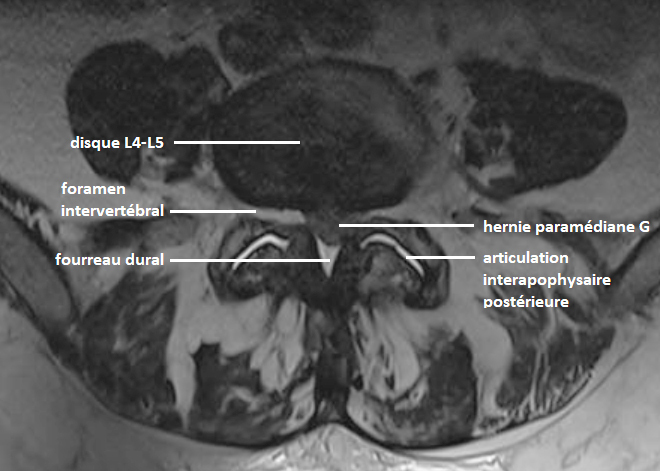

Par argument de fréquence, vous suspectez une lombosciatique L5 gauche non compliquée sur hernie discale.